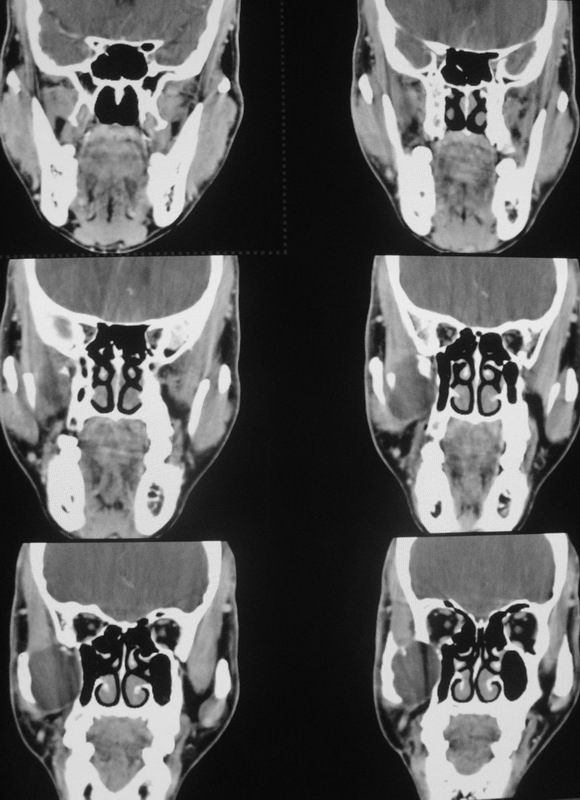

以下是引用zsl6918在2008-5-6 14:41:00的发言:[br]右侧颞下窝内囊性占位(增强未见强化),同侧上颌窦受压变形移位,提示慢性过程。右侧上颌骨局限性吸收破坏,提示良性病变。

以下是引用长城干红在2008-5-6 15:05:00的发言:[br]考虑:右侧颞下窝神经源性良性肿瘤。

以下是引用xuhuihong在2008-5-6 14:57:00的发言:[br]右侧颞下窝内囊性占位(增强未见强化),同侧上颌窦受压变形移位骨质吸收变薄,提示慢性过程。右侧上颌骨局限性吸收破坏,提示良性病变。考虑神经源性肿瘤可能,期待结果。